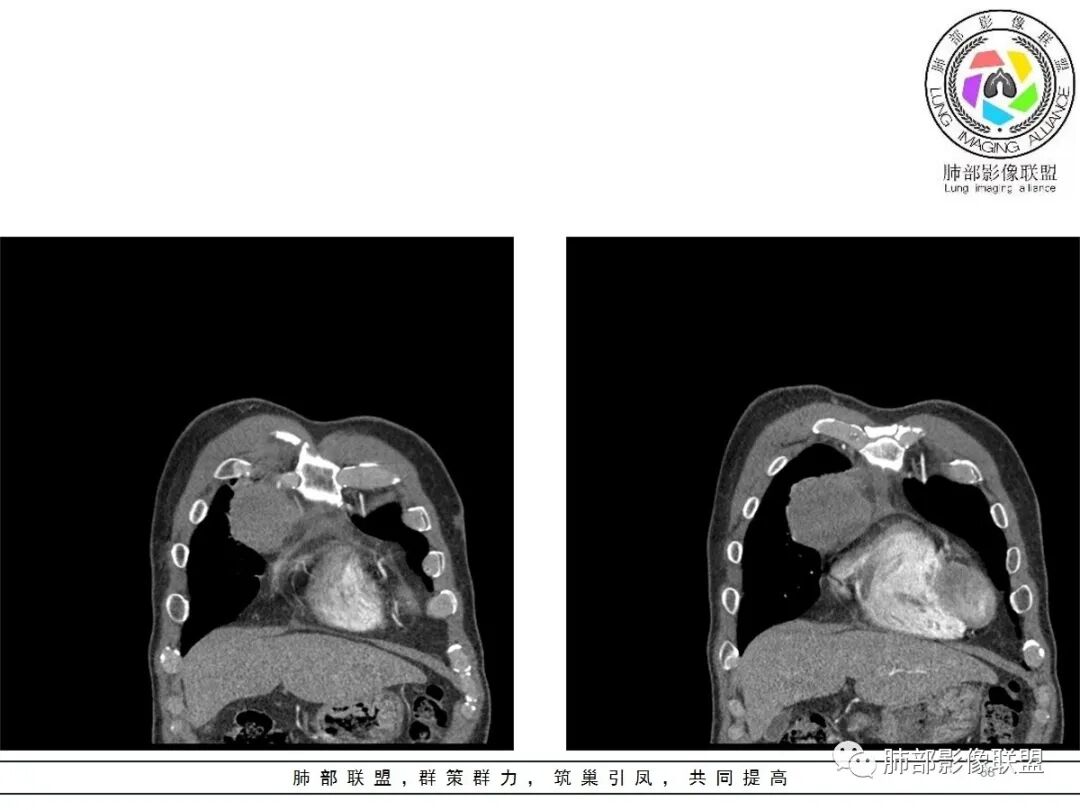

大雄:老年男性  急性起病 胸痛1天前纵隔占位伴右侧少量胸水,肿块整体膨隆,密度不均匀,可见坏死,纵隔脂肪间隙模糊不清常规考虑胸腺瘤/癌并梗死

一切∮随缘:定位肺外,病变位于右前纵隔,与肺部交接面清晰,有胸膜尾征,心包局部受压,部分包绕主动脉血管,平扫密度均匀,形态规则,膨胀性生长,增强扫描壁有强化,内容物无明显强化,考虑1:淋巴瘤2:胸腺瘤3:神经鞘瘤4:支气管囊肿

亚东:前纵隔囊实性肿物,形态尚规则 ,与心包分界不清,内可见小气泡,嚢内平扫密度低,强化不明显,囊壁强化,右胸腔积液,淋巴结肿大不明显,化验白细胞高,支持囊肿伴感染。

小强:前纵隔肿块,边缘模糊,其内有点状气体影,环形强化(肉芽肿?),心包胸膜受累,疾病谱:胸腺瘤(一般是侵袭性胸腺瘤累计心包,胸膜,强化不符合)淋巴瘤,生殖细胞瘤(年龄,AFP不高不负),考虑畸胎瘤,囊性畸胎瘤合并感染,边缘模糊,累计心包胸膜,3.19病变进展,胸腔积液,可能有破溃

采莲:老年男性,胸疼病史,右上前纵隔肿块,边缘光滑,平扫内部密度稍均匀,轻度强化,内有低密度区,与支气管关系不大,右侧少量积液。考虑来源纵隔,老年男性,胸腺瘤或胸腺癌,鉴别淋巴瘤。

冥冥之中:定位,右前纵隔

定性,肿块边缘模糊,右侧胸腔积液,上腔静脉边缘侵袭,恶性

年龄68常规考虑胸腺癌,但是里面有脂肪成分,周边有钙化,畸胎瘤不能排除

综合考虑,前纵隔恶性病变,畸胎瘤>胸腺癌

2.胸膜掀起,右侧内乳动脉略增粗,定位右前上纵隔内占位。

3.右上纵隔囊实性占位,边界清楚。中央见点状脂肪密度影,边缘见一点状钙化影,增强不均匀环形强化。

4.四天内病灶变化快,块影增大且不规则,包膜似不完整,边界不清,上份可见浸润或渗出,与周围心脏大血管及心包等间隙不清。胸水增多。